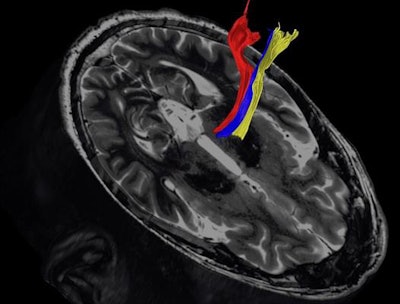

- Diffusion tractography, an FDA-approved method that creates 3D white-matter maps from diffusion-weighted imaging (DWI) -- which is an MRI sequence sensitive to water movement within tissues. "DWI can serve as an indirect measurement of anisotropy and structural organization of white matter," the group wrote.

Diffusion tractography uses the movement of water molecules to identify tracts that connect different parts of the brain. It can be used to pinpoint the part of the thalamus to treat with focused ultrasound. Image courtesy of the University of Texas Southwestern Medical Center.These techniques show promise in identifying diseased tissue caused by Parkinson's or essential tremor, the group wrote. In fact, Shah and colleagues plan to participate in a multicenter clinical trial with collaborators at the Mayo Clinic in Rochester, MN, testing the diffusion tractography method in patients, according to the university statement.